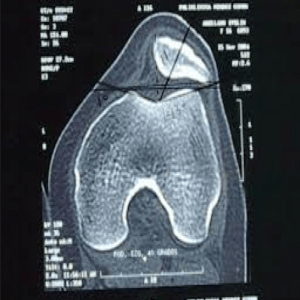

TAC rodilla